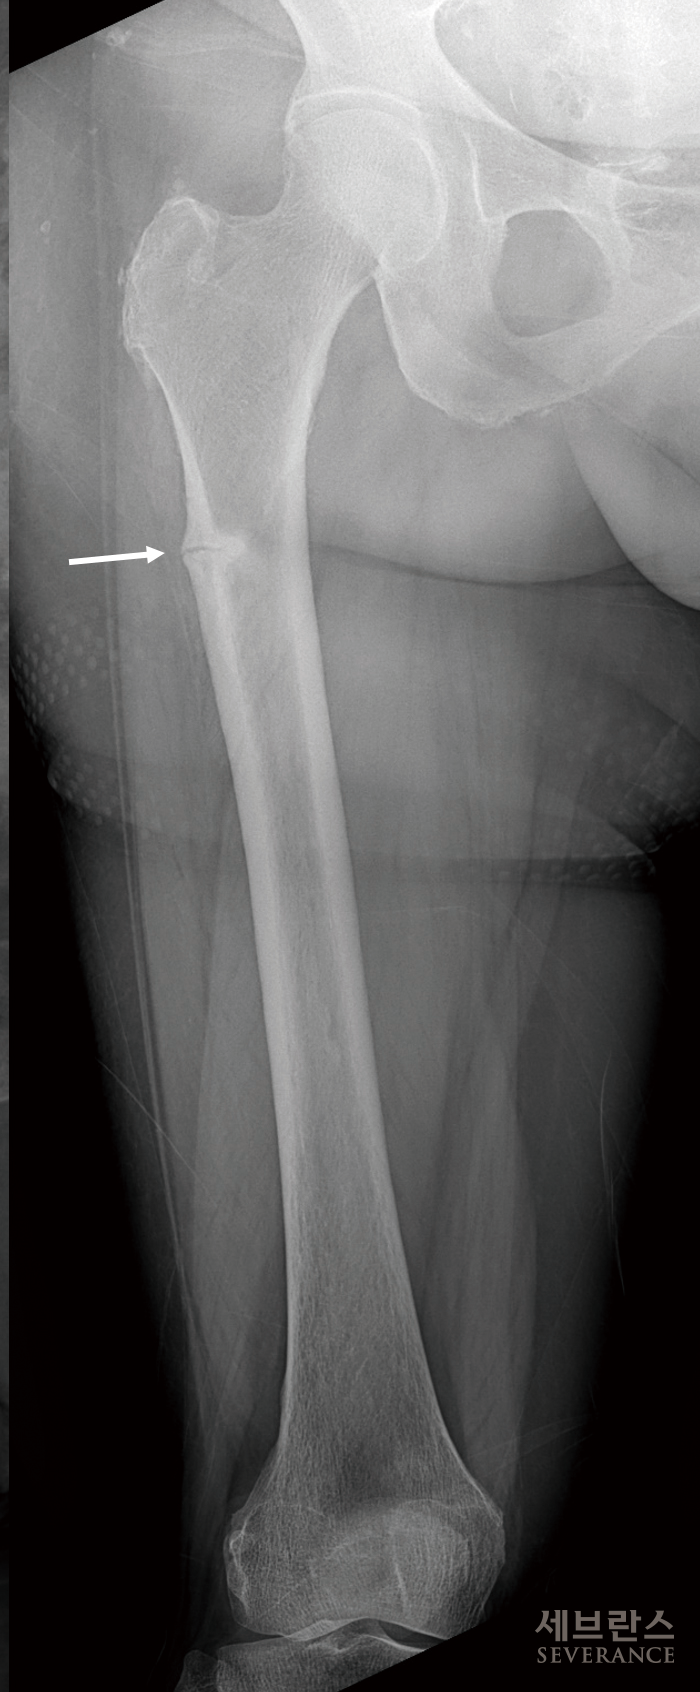

발생 원인은 명확하지 않으나 주로 골다공증 치료를 오래 지속한 환자에서 대퇴골 전자 하부 또는 몸통부의 바깥쪽에 금이 가다가 골절되는 것으로, 일반적인 대퇴골 골절과 달리 질환의 일종입니다. 뚜렷한 외상이 없거나 가벼운 외상으로도 골절이 일어나고, 특이한 골절 형태를 보입니다.

대퇴골 골절 수술은 일반적으로 다른 부위의 골절처럼 뼈를 붙이는 치료를 하고, 고령의 대퇴경부 골절 환자에서는 인공관절 치환술을 하기도 합니다. 전신 또는 척추마취가 필요하며 골절로 어긋난 뼈를 잘 맞춘 뒤 여러 금속 기구를 이용해 적절하게 고정시킵니다.(금속판, 금속정) 많은 환자들이 수술 후 초기에 뼈가 잘 붙고 있는지 궁금해합니다. 골유합에 필요한 시간은 개인마다 차이가 있으며, 보통 3-6개월 정도 걸립니다. 수술 후 외래진료에서 일반 방사선검사를 시행해 고정된 뼈가 움직이는지, 삽입된 금속에 문제가 없는지 등을 확인하는데, 이때 뼈가 잘 고정되어 있고 금속 주위에 문제가 없으면 대부분 골유합이 잘 이루어집니다.